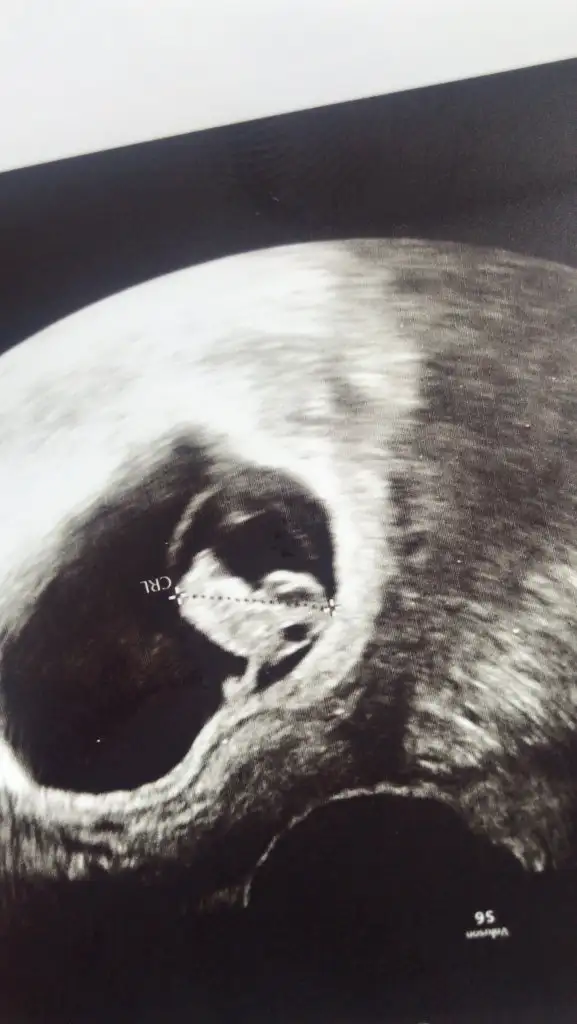

Teoriye göre kizBu kız kardeşimin bebeği cinsiyeti belli oldu sizce nedir

Eki Görüntüle 2788863

6-7 hafta arası varsa yorumlayabilirim ama uzman değilim öyle eğlencesineEki Görüntüle 2789978 lutfen yorum yaparmisiniz kizmi erkekmi